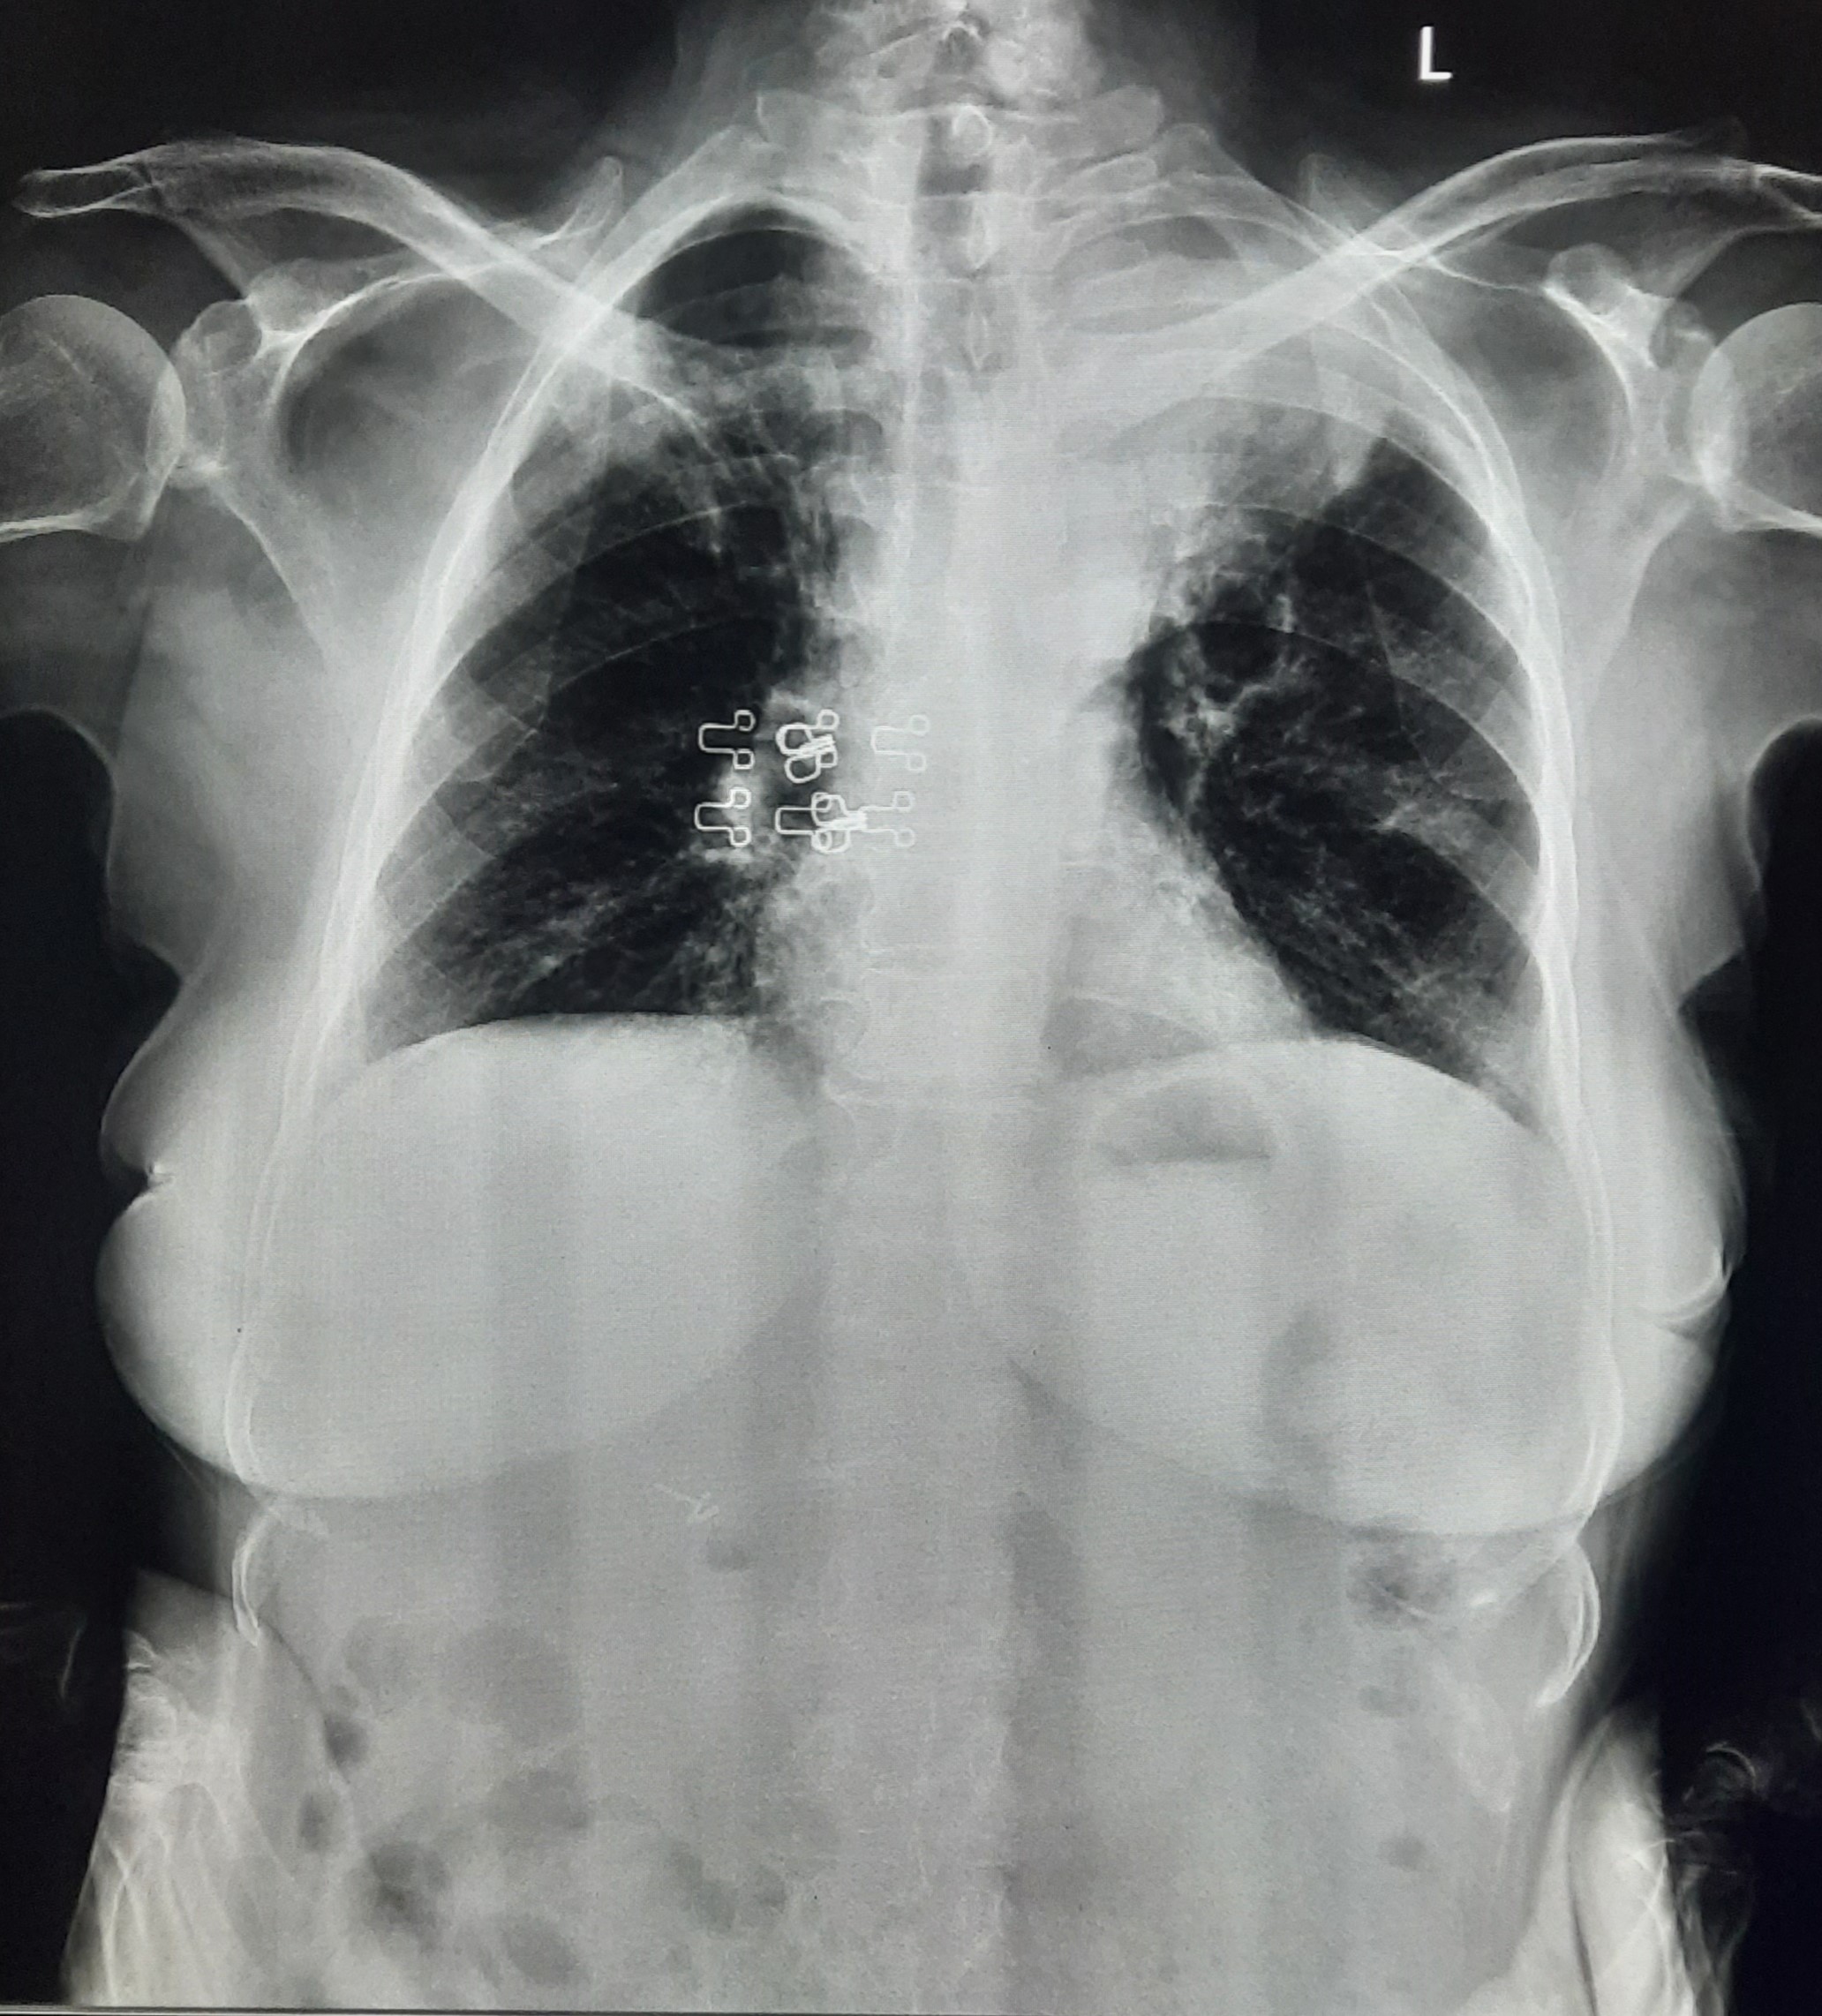

| 127 | IGGMC, Nagpur, Nagpur | P2 | 29-4345 | Hiraman Tembhurne | Consent taken on Paper | 62 Yrs. |

Provisional Diag : Dyspnea

Final Diag : Post TB With Interstitial Lung Disease |

Post TB Sequelae | Bilateral Cystic Opacity Upper, Mid & Lower Zone/ Bilateral Reticular Opacites/ Bilateral Fibrotic Bands Present/ Decrease Lung Volume/ Few Old Calcific Nodules | Abnormality visible on x-ray |